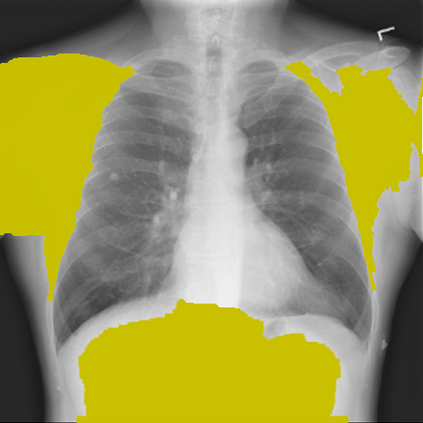

The remarkable success of deep learning has prompted interest in its application to medical imaging diagnosis. Even though state-of-the-art deep learning models have achieved human-level accuracy on the classification of different types of medical data, these models are hardly adopted in clinical workflows, mainly due to their lack of interpretability. The black-box-ness of deep learning models has raised the need for devising strategies to explain the decision process of these models, leading to the creation of the topic of eXplainable Artificial Intelligence (XAI). In this context, we provide a thorough survey of XAI applied to medical imaging diagnosis, including visual, textual, example-based and concept-based explanation methods. Moreover, this work reviews the existing medical imaging datasets and the existing metrics for evaluating the quality of the explanations. In addition, we include a performance comparison among a set of report generation-based methods. Finally, the major challenges in applying XAI to medical imaging and the future research directions on the topic are also discussed.